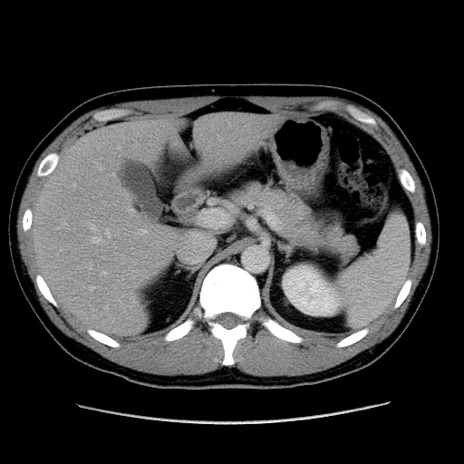

冠状断像

【症例】30歳代男性

【主訴】腹痛、嘔吐

【現病歴】昨晩から突然の腹痛あり、その後嘔吐、軟便も出現。腹痛が改善しないため救急搬送となる。2日前にしめ鯖の食事歴あり。

【身体所見】意識清明、苦悶様、BP 135/90mmHg、BT 35.7℃、腹部:平坦、やや硬、心窩部〜臍部に自発痛、圧痛あり、筋性防御+、反跳痛-

【データ】WBC 8100、CRP 0.57